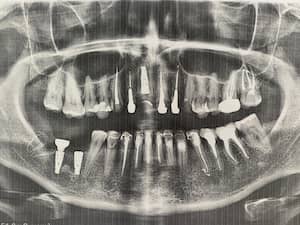

До

После

Удаление 7 зубов, установка 11 имплантов Straumann, временное и постоянное протезирование всех зубов с учетом формы, цвета и размера зубов. Работа с мягкими тканями. Импланты использовались для немедленной нагрузки.